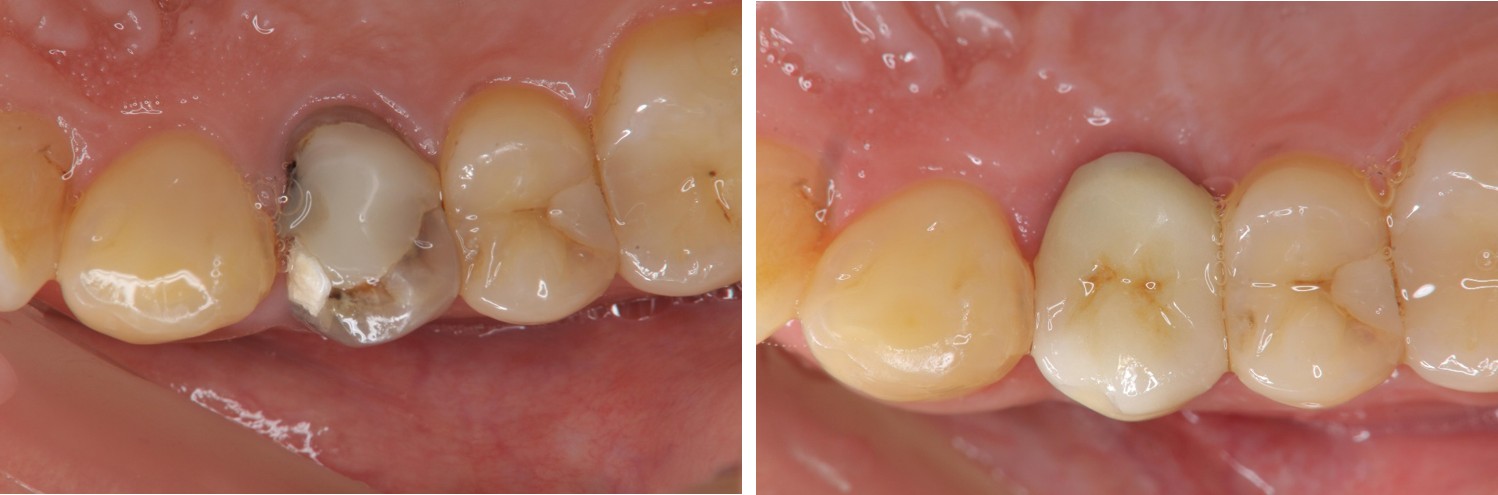

水雷射牙冠增長手術

鑄造金屬釘柱

全鋯冠

治療後,密合度良好

術前、術後比較